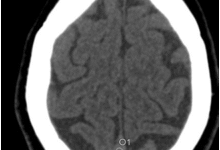

Much effort is being expended to determine the mechanism of action of this condition as a prerequisite to seeking an effective treatment. Published work suggest a role for the Mast Cells and/or Ion Channels and/or Genetics as playing a key role. In addition, suggestions will be presented for new areas of research to be investigated. These include non-canonical DNA structures as a target for chemical binding. The role of the microbiota in modifying chemical activity will be discussed. Histopathological approaches will be suggested. In particular, it will be proposed that just as there are characteristic features of different lung pathologies, so, too, perhaps, there is a unique presentation at the WSI level that, together with AI analysis, might provide important clues as to the etiology and pathological mechanism of MCS. Attendees are invited to contribute their expertise to help solve this problematic puzzle of pathology.